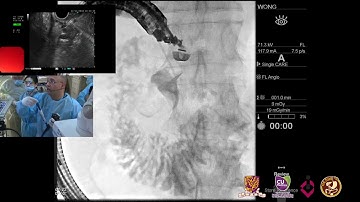

ERCP ; Simple cannulation of recently passing stone cholangitis case.